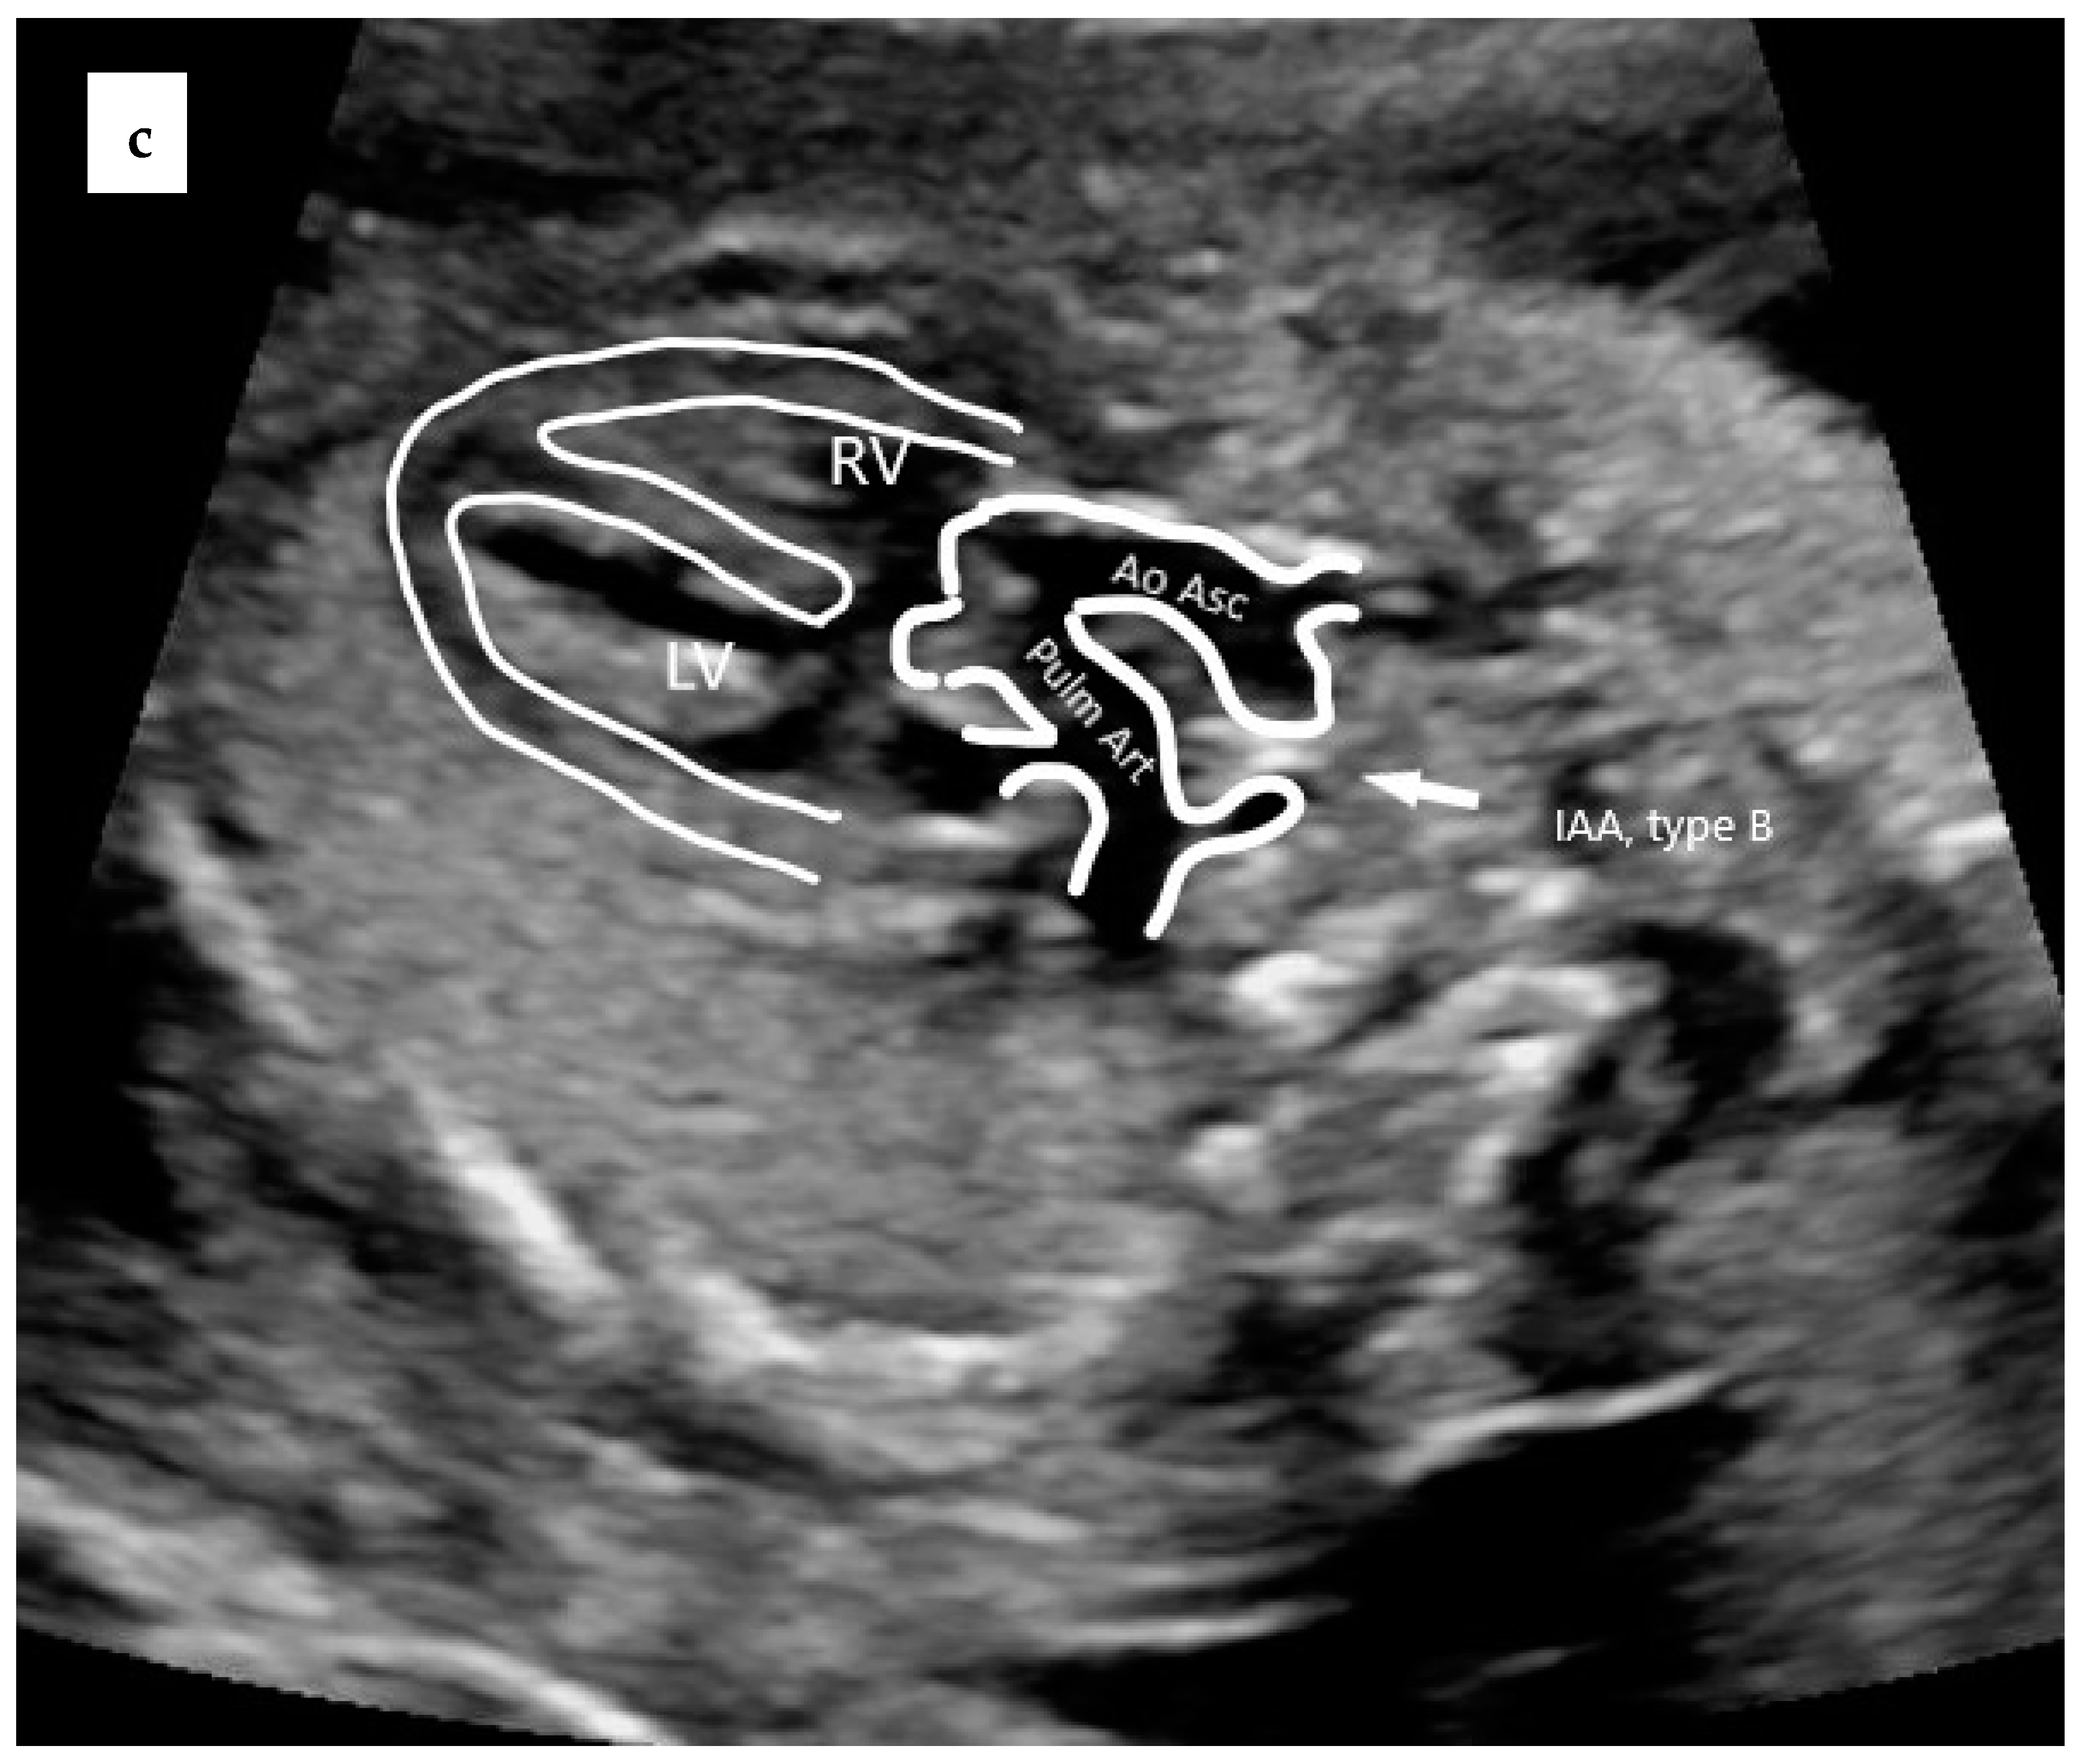

- Mărginean, C.; Gozar, L.; Mărginean, C.O.; Suciu, H.; Togănel, R.; Muntean, I.; Mureşan, M.C. Prenatal diagnosis of the fetal common arterial trunk. A case series. Med. Ultrason. 2018, 20, 100–104. [Google Scholar] [CrossRef]